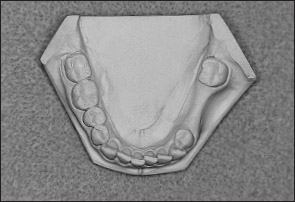

• Kennedy Class II arch: Displays a unilateral edentulous area located posterior to the remaining natural teeth (Figs 1-13 and 1-14).

Fig 1-14 Mandibular Kennedy Class II arch.